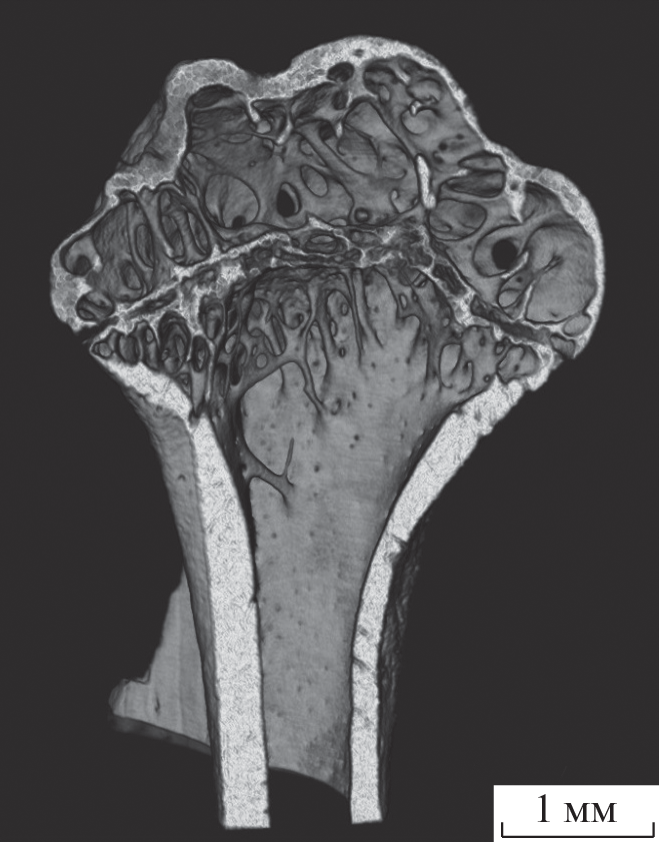

Разработан опытный образец лабораторного конусно-лучевого рентгеновского микротомографа. Микротомограф собран на базе микрофокусного источника рентгеновского излучения, работающего в диапазоне ускоряющих напряжений 30–80 кВ. Проведена автоматизация работы микротомографа, создано программное обеспечение для реконструкции трехмерных изображений. Продемонстрированы результаты томографический исследований нескольких тестовых объектов с разрешением менее 10 мкм.